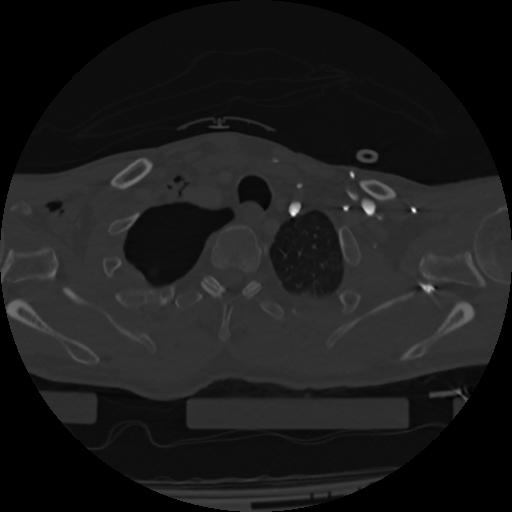

22 ANGIO,CE,Vol,0.5,ANGIO,,